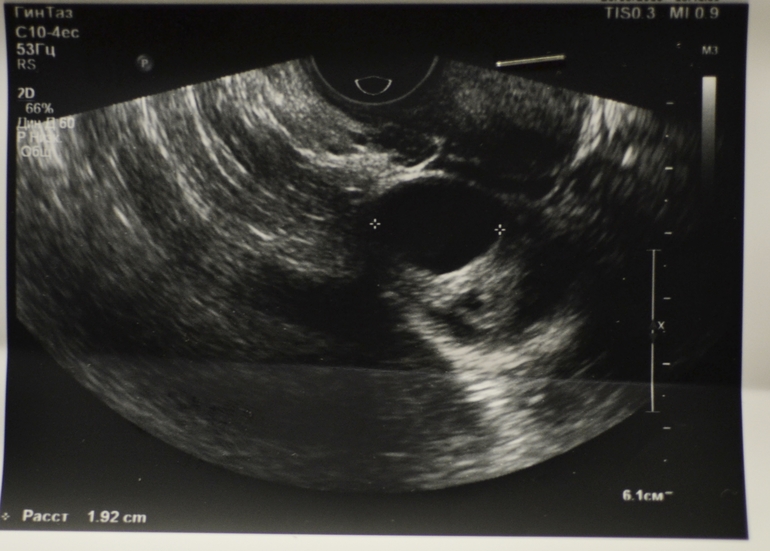

Желтое тело или киста ?

ФолликулометрияДорогие девушки , кто сталкивался с тем , что не могли определить на узи - чем является анэхогенное образование? Прошу помощи , так как уже бессонница от того , что не знаю с чем столкнулась. К гинекологу записана на четверг следующей недели.Может ли это быть жёлтое тело ? 21 день задержки. Три теста отрицательные. По результатам узи :

Скорее всего фоликулярная киста, края ровные у жт не такие, фоликулярные часто вызывают задержку

Мне кажется, что это киста желтого тела. Исходя из того, что есть жидкость в области малого таза. Киста вырабатывает много прогестерона, от нее бывают задержки.

Размеры : 31*28*34

Форма :грушевидная

Структура миометрия : однородная

Эхогенность :средняя

Шейка матки : 33*21 мм, толщина эндоцервикса в 1 слой 4мм,церквиальный канал расширен на всём протяжении до 1,5 мм. Васкуляризация шейки умеренная.

Эндометрий :6 мм толщиной

Структура : однородная

Эхогенность : изогиперэхогенная в 2 слоя

Контуры : ровные ,чёткие

Очаговые изменения : нет

Полость матки : не расширена

Узи от 20.03.16

Исходя из УЗИ Б нет.. Матка не увеличена. Но если все таки питаете надежды, то самый верный способ сдать кровь на ХГЧ.